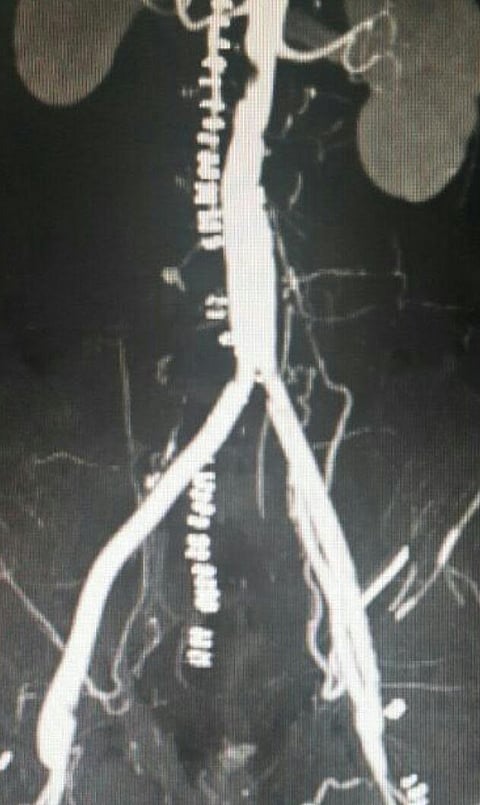

وكان المريض يشكو من آلام شديدة بالطرفين السفليين مع برودة بالقدم وعدم القدرة على السير، وبعد فحص المريض وعمل التصوير الطبقي للشرايين تبين وجود انسداد في الشريان الأبهر البطني وكذلك الشرايين الحرقفية الأيمن والأيسر حتى الشرايين الفخذية.

وتمت العملية بوصل شريان صناعي مع الشريان الأبهر البطني ووصله بالشريان الفخذي الأيمن والأيسر ليتم إيصال الدم الشرياني إلى الطرفين السفليين وتجاوز منطقة الانسداد بالأبهر البطني والشريانين الحرقفيين.